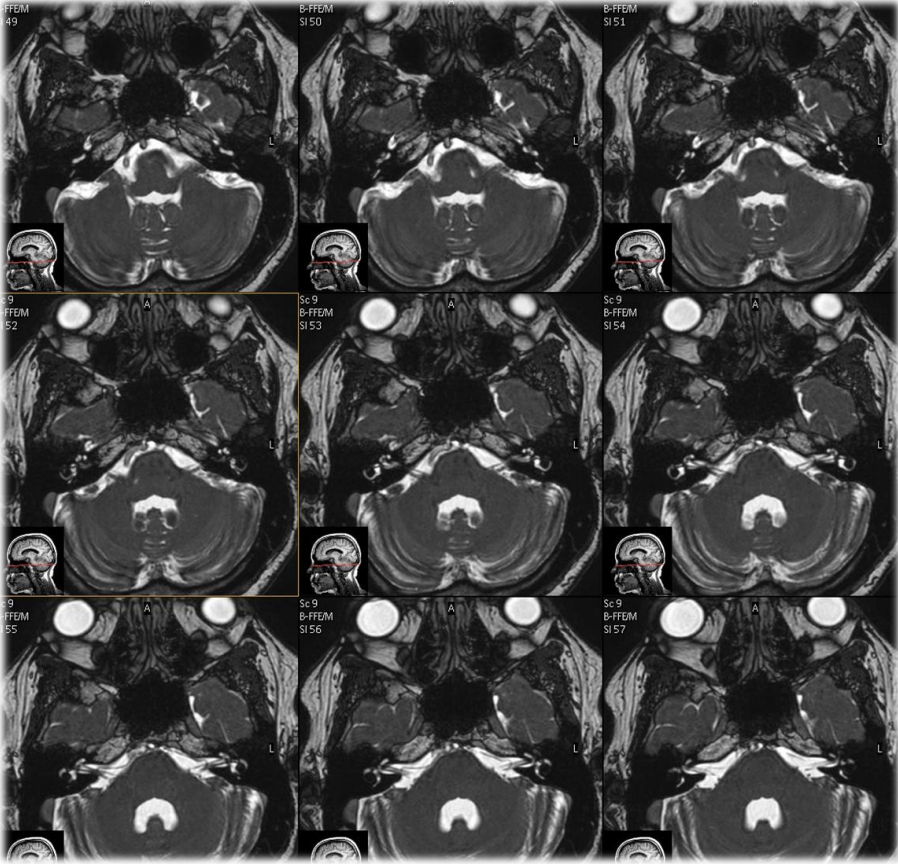

BTFE sequences are and are quipped with

variations of high T2 signal, balanced steady state sequences

equipped with slice, phase and frequency rewinder pulses, yielding images with mixed contrast T2/T1

BTFE sequences look like

image of high SNR with bright fluids, particularly useful in evaluation of cranial nerves